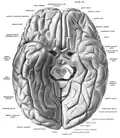

Базальная поверхность мозга, прямая извилина отмечена в верхней части